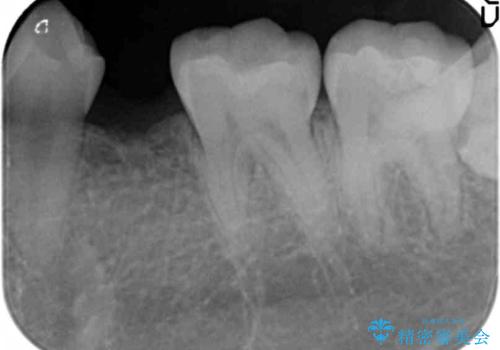

- 左下の奥歯が生まれつき歯が少ない患者様です。

健康な歯を削らずに歯を入れたいとのことでした。

歯がなかった時期に隣の歯が移動してすき間があったため、部分的な矯正治療を行い、インプラントを入れるすき間を確保しています。